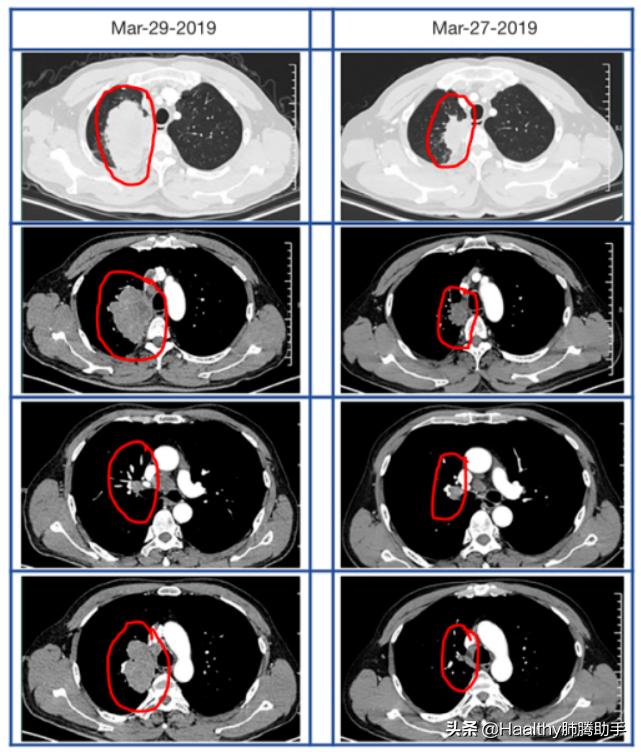

新辅助免疫治疗呢?这里也有一个例子。某男性患者被最终诊断为IIIB期(T4N2M0)肺腺癌,且驱动基因阴性。胸部CT扫描显示患者右上肺的异物性浸润性肿块达到7.7 cm×6.2 cm。接受每3周用培美曲塞和卡铂联合200 mg派姆单抗一起治疗。2个周期的化学免疫治疗后,再次进行胸部CT扫描显示,发现右上肺肿块缩小至4.6 cm,纵隔和肺门淋巴结缩小;血浆肿瘤标志物水平持续下降,CEA,CyFra21-1和NSE恢复至正常水平。之后,该患者接受手术治疗。最终的病理报告显示为5.5cm T3N2腺癌,成功实现了降期后的手术根治。

化疗联合免疫治疗后,肺肿块以及纵隔和肺门淋巴结明显缩小